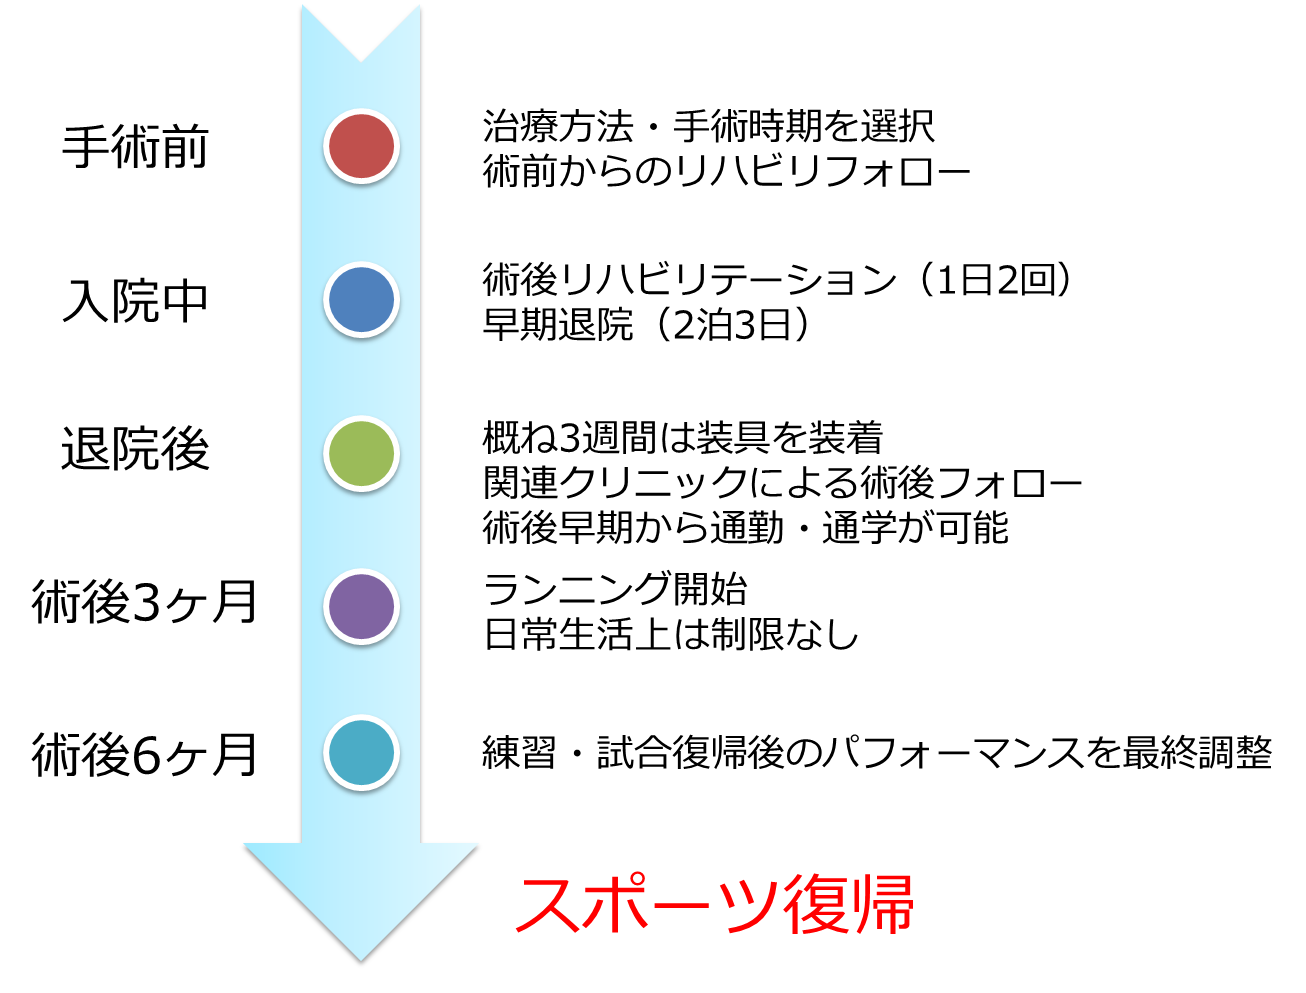

手術前から手術後までの流れは?

手術後、約3週までは装具を外した状態でも生活ができるようなリハビリが中心となります。装具固定期間が過ぎると積極的に肩関節の柔軟性向上を図ります。それと同時に体幹や肩甲骨周囲のトレーニングを出来る範囲で行なっていき、術後3ヶ月頃から積極的なトレーニングを開始します。術後4か月以降には可能な練習に徐々に参加し、概ね術後6ヶ月で復帰が可能となります。

- A.1 概ね術後4ヶ月から徐々に練習に参加し,6ヶ月での完全復帰が目標となります。